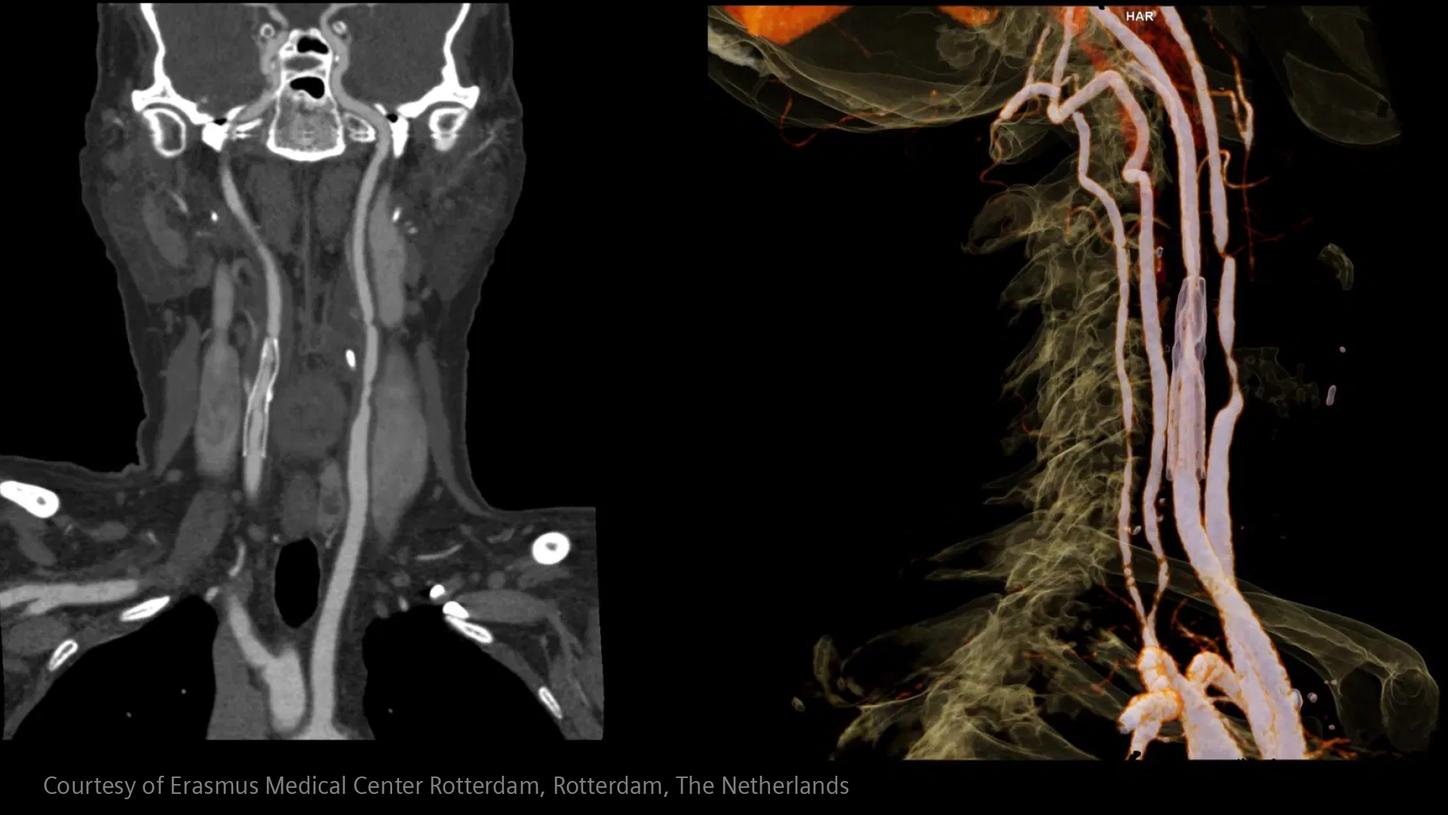

Critical insights in seconds:

How advanced imaging and AI transform stroke workflow

In stroke care, time is brain. Rapid and accurate imaging is crucial to assess the extent of brain injury and guide immediate treatment. Angiography, MRI, CT, ultrasound, and lab diagnostics are essential tools in identifying stroke type, location, and severity. Advances in imaging technology now allow for even faster acquisition, improved resolution, and enhanced visualization of brain tissue and blood vessels. Innovations such as perfusion imaging, real-time vascular mapping, and AI-assisted diagnostics are transforming stroke workflows and enabling precise, timely interventions.